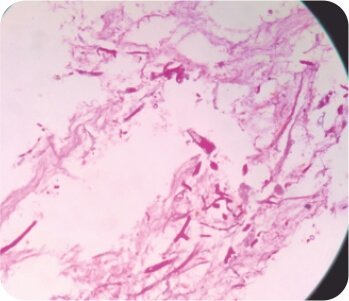

সিটি বুক বাম উপরের লোবে গহ্বরের ইঙ্গিত দেয়। এফওবি বাম উপরের লোব ব্রঙ্কাস থেকে পুস নির্গত হওয়ার পরামর্শ দিয়েছিল এবং বাম উপরের লোব ব্রঙ্কাসে একটি জমাট ভরের সাথে অনুগত। পরবর্তী ব্রঙ্কোঅ্যালভিওলার ল্যাভেজ প্রধানত নিউট্রোফিলিক ছিল। পাইজেনিক, ছত্রাক, যক্ষ্মা এবং নোকার্ডিয়ার জন্য দাগ এবং সংস্কৃতি নেতিবাচক ছিল। সাইটোলজি ম্যালিগন্যান্সির জন্য নেতিবাচক ছিল। ইনভেসিভ মিউকোরমাইকোসিসের একটি নির্ণয় করা হয়েছিল।

আক্রমণাত্মক মিউকার মাইকোসিস (ব্রড অ্যাসেপ্টেট হাইফা) এর প্রসারিত ভরের ক্রিবায়োপসি